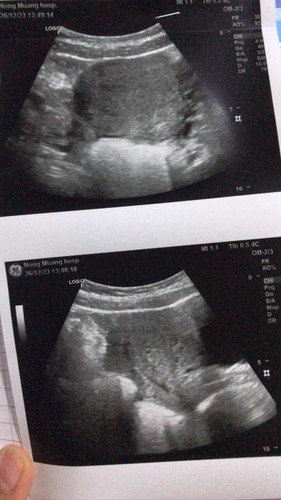

ท้องได้5week แต่ไปซาวด์ไม่เจออะไรเลยแบบนี้ผิดปกติมั้ย ถุงตั้งครรภ์รึตัวอ่อนก็ไม่เจอเลย

อายุครรภ์ประมาณนี้ ซาวด์ไม่เจออันตรายมั้ยคะ กลัวท้องนอกท้องลมมาก

บ้านนี้ไปซาวด์ตอน5วีคก็ไม่เห็นค่ะน้องเล็กมากนะคะ นอกจากคุณแม่จะซาวผ่านมดลูก บ้านนี้คุณหมอนัดซาวอีกทีตอน8วีคถึงพบน้องค่ะ

เราไปตอนตรวจเจอสองขีด ไปซาวดูก็ไม่เจออะไรค่ะ หมอบอกอีก 1 เดือนมาซาวใหม่นี้ก็รอวันที่5 นี้ตื่นเต้นมากค่ะ